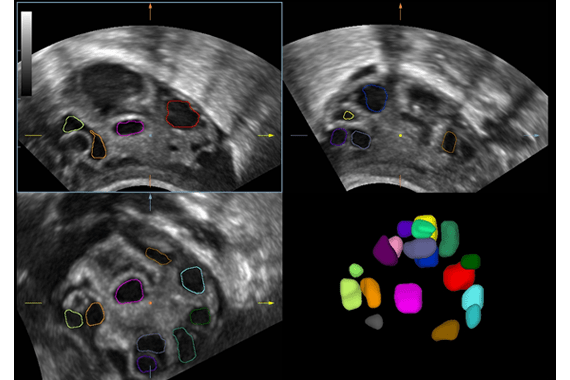

- iPage – мультисрезовое томографическое изображение

- Функции, поддерживаемые УЗ датчиками: THI, Smart3D, 4D, iScape, TDI, цветной M режим, эластография, биопсия